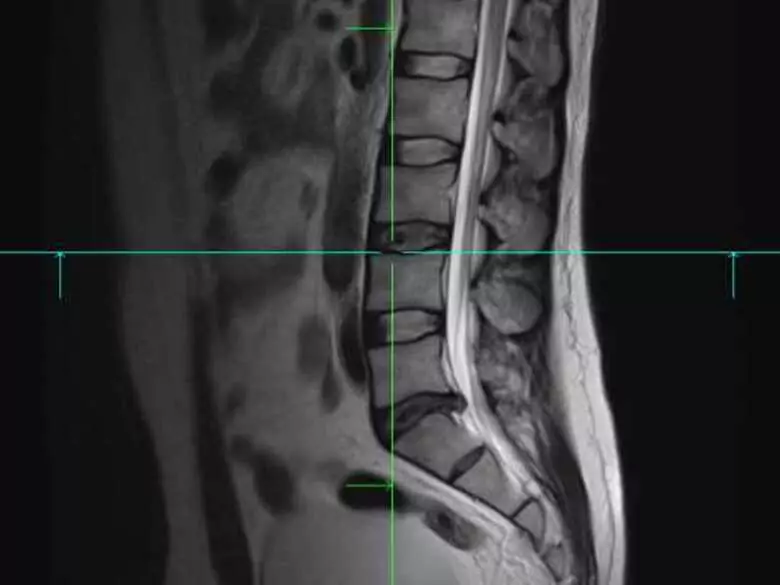

Dyskopatia to nic innego jak wypadnięcie krążka międzykręgowego z miejsca, jego naturalnego położenia. W większości przypadków, dyskopatie obejmują najczęściej dolny odcinek kręgosłupa (odcinek krzyżowy oraz lędźwiowy).